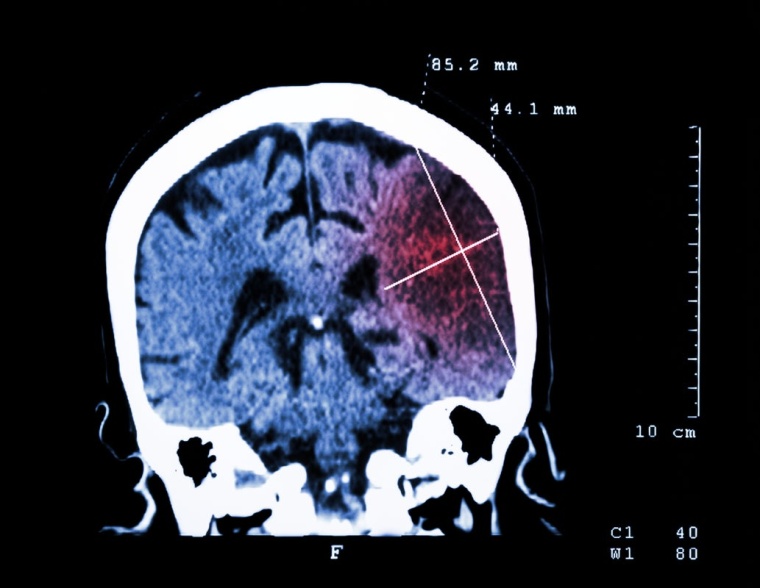

Schlaganfall: Entzündung, zweite Stufe

Etwa 200.000 Bundesbürger erleiden Jahr für Jahr einen Schlaganfall. Er ist damit die zweithäufigste Todesursache - und ein Hauptgrund von Behinderung im Erwachsenenalter. Meist wird der Schlaganfall verursacht durch eine Arteriosklerose, im Volksmund auch Arterienverkalkung genannt. Zu diesem Prozess kommt es, wenn Immun- und Entzündungszellen in Fettablagerungen in die Wand von Blutgefäßen einwandern. In den entstehenden "Plaques" baut sich eine schädliche Entzündungsreaktion auf, die sich verselbstständigt, chronisch wird, zu Verkalkungen und Engstellen führt und die Gefäße verstopft. Mehr noch: Aus diesen "Plaques" können sich Gerinnsel lösen, durchs Blut wandern und kleine Gefäße im Gehirn blockieren. Warum es aber bei gut zehn Prozent der Patienten selbst bei bester Versorgung im Krankenhaus binnen Tagen und Wochen zu weiteren Schlaganfällen kommt, blieb lange ungeklärt.